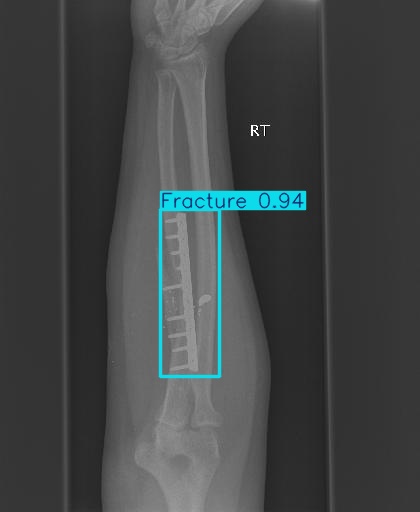

Bone 이미지 데이터 350장 중 Fracture 이미지 50장, Implant 이미지 50장, Bone 이미지 50장을 선별했다.

train과 val은 라벨링을 해야한다. 어제 라벨링을 했었지만, Fracture는 좀 넓게 잡고, Implant는 최대한 여러개로 쪼개는 느낌으로 라벨링을 다시했다.

진짜 라벨링 문제였나보다

그리고 predict 단계에서 IoU( Intersection over Union )를 낮추란다. 낮춰보자

IoU는 '교집합 영역 넓이 / 합집합 영역 넓이' 이다.